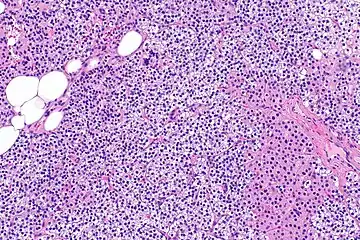

Parathyroid hyperplasia low mag. -

Parathyroid hyperplasia medium mag. -

Parathyroid hyperplasia high mag.

Primary hyperplasia of the parathyroid gland, results from both hypocalcaemia and increased phosphate levels by decreasing expression of calcium sensing receptors and vitamin D receptors at the parathyroid gland.[8][4] These decreases in receptor expression lead to hyperfunctioning of the parathyroid. Hyperfunction of the parathyroid gland is thought to exacerbate primary hyperplasia which evolves further to a secondary more aggressive hyperplasia. Histologically, these hyperplasic glands can be either diffuse or nodular.[24] Primary hyperplasia, usually resulting in diffuse polyclonal growth is manly related to reversible secondary hyperparathyroidism. Secondary hyperplasia of the parathyroid gland is more often a nodular, monoclonal growth that sustains secondary hyperparathyroidism and is the catalyst in the progression to tertiary hyperparathyroidism. Nodular hyperplastic glands in tertiary hyperparathyroidism are distinctly larger in both absolute size and weight up to 20-40-fold increases have been reported.[25][26][24]

Parathyroid glands are normally composed of chief cells, adipocytes and scattered oxyphil cells.[27][14] Chief cells are thought to be responsible for the production, storage and secretion of parathyroid hormone. These cells appear light and dark with a prominent Golgi body and endoplasmic reticulum. In electron micrographs, secretory vesicles can be seen in and around the Golgi and at the cell membrane. These cells also contain prominent cytoplasmic adipose.[27][14] Upon onset of hyperplasia these cells are described as having a nodular pattern with enlargement of protein synthesis machinery such as the endoplasmic reticulum and Golgi. Increased secretory vesicles are seen and decreased intercellular fat is characteristic.[27][24] Oxyphil cells also appear hyperplasic however, these cells are much less prominent.